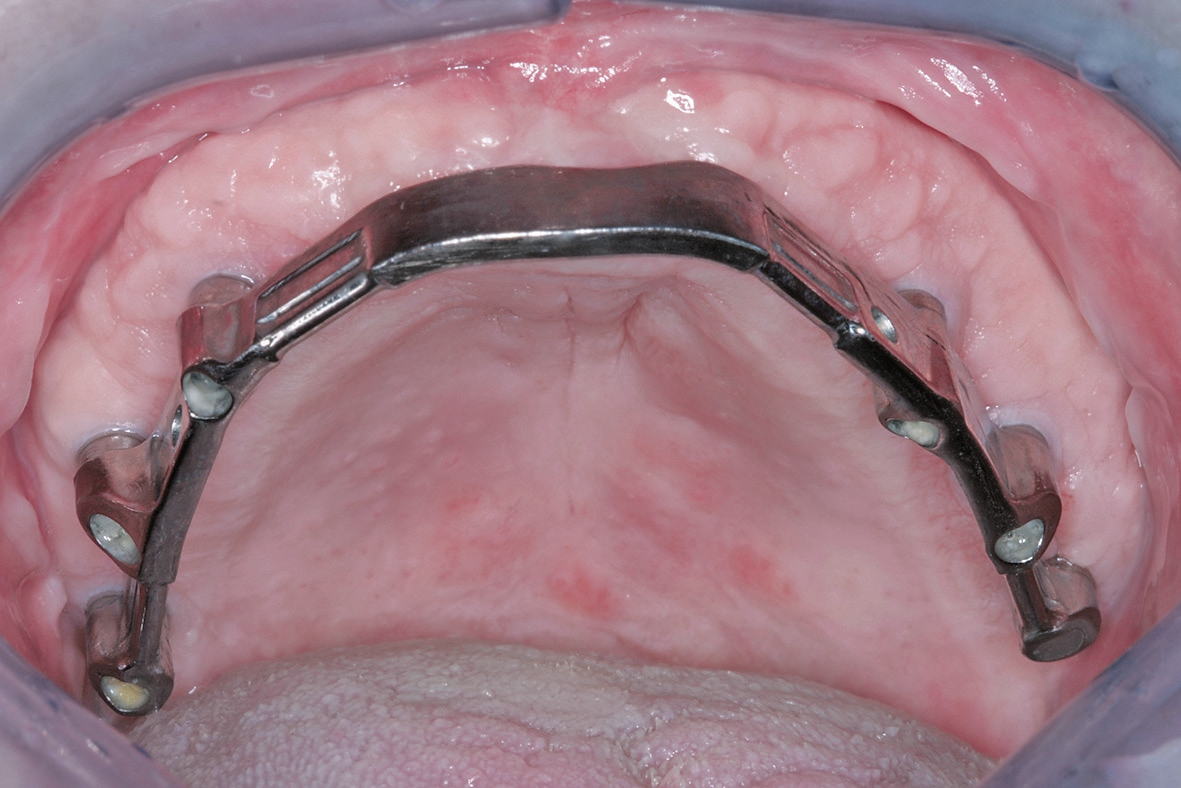

Zurück im Labor wurde der fertige Steg bei perfekter Passung auf dem Meistermodell verschraubt und in der nächsten Sitzung anprobiert (Abb. 16a u. b).

Dr. Zastrow